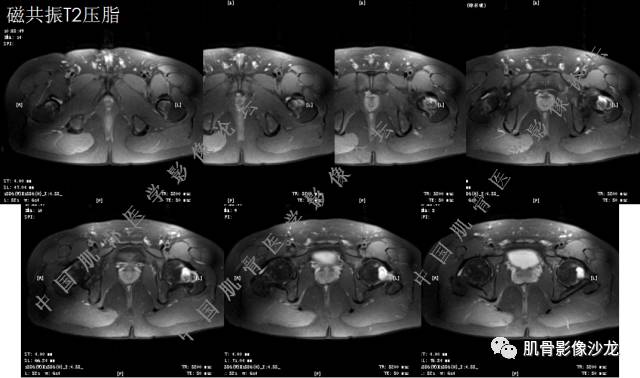

主诉:左髋疼痛1月余

现病史:患者1月余前无明显诱因出现左髋部疼痛,无明显活动受限,当地医院行X线检查,提示左股骨颈异常密度。遂来我院就诊。

既往史:曾患乙型肝炎,未正规治疗,目前无症状。

葛英霖 20:5 4 常规纤维类的多一些,冠状位没有看到明显脂肪。纤维结构不良、纤维组织细胞瘤、软粘纤之类。

夏威夷的风 20:55 大方向纤维类病变

夏威夷的风 20:58 强化渐进性强化吧 边界清晰 里面也见线状低信号

飞鹰行动 21:01 良性纤维组织细胞瘤内部可以有少量脂肪

X(CT、MR)战警 21:01 泡沫细胞被吞噬后形成脂肪信号, bfh可以有脂肪条带样改变

Echo 21:04 总之这例就是各位老师说的硬化边明显,没有软组织肿块,没有侵犯,考虑良性病变,增强渐进性强化,所以考虑BFH